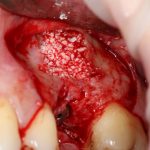

Простой синуслифтинг. Часть I.